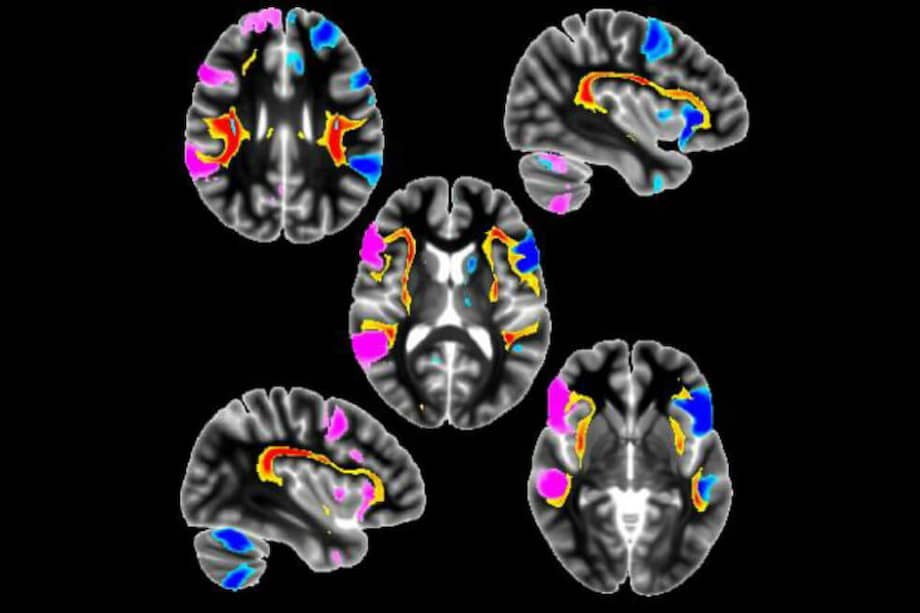

Los científicos procesaron escáneres cerebrales y examinaron los genomas de los participantes para encontrar las conexiones entre el uso del lado zurdo, las estructuras en el cerebro y las diferencias en los genes.

Los resultados de la búsqueda de correlaciones entre las características estructurales del cerebro y el uso de la mano izquierda mostraron que las personas zurdas tienen una conexión más fuerte entre los centros del habla de diferentes hemisferios. Además, existen características comunes de los tractos que conectan los centros del habla en personas zurdas y pacientes con esquizofrenia y que sufren de alucinaciones auditivas.